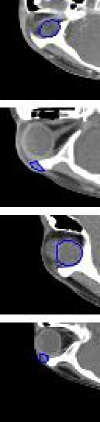

To evaluate the proposed method, we conducted a 10-fold cross-validation procedure for the PDDCA dataset, and a 4-fold cross-validation procedure for the orbital tumor dataset. Table II shows the quantitative segmentation comparison results of the proposed method with the state-of-the-art methods on the two test datasets. The numbers are the mean and standard deviation values computed through cross-validation. The results show that the proposed method achieved the best performance in terms of two measurements. The score differences on the orbital tumor are significantly higher than the ones on the PDDCA. These results imply that the proposed method provides better segmentation performance, and has particularly strong advantages from a small number of training data. A few segmentation results of PDDCA and CMC-ORBIT are shown in Fig. 2 and Fig. 3.

The effects of domain adaption have been visualized in the Figs. 2 and 3. Application of domain adaptation to SEQ-UNET, improved DICE and VS much more than transfer learning as shown in Table III. When sensitivity and specificity were measured in the CMC-ORBIT, we found that SEQ-UNET + DA improved sensitivity, while SEQ-UNET + TR exhibited a performance similar to SEQ-UNET as shown in Table IV.